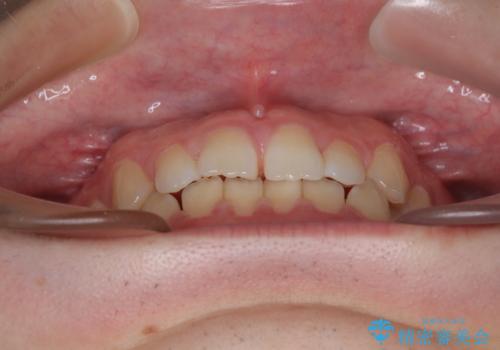

- 「前歯のすきっ歯が気になる」「食べ物が歯の間に詰まりやすい」とのお悩みで来院された20代男性の患者様です。

歯と歯の間に隙間がある**空隙歯列(すきっ歯)**は、見た目の問題だけでなく、食片圧入による歯肉の腫れや、隣接面う蝕のリスク増加につながることがあります。

診査により舌突出癖が認められました。この癖は、すきっ歯の原因となるだけでなく、矯正後の後戻りリスクを高めます。